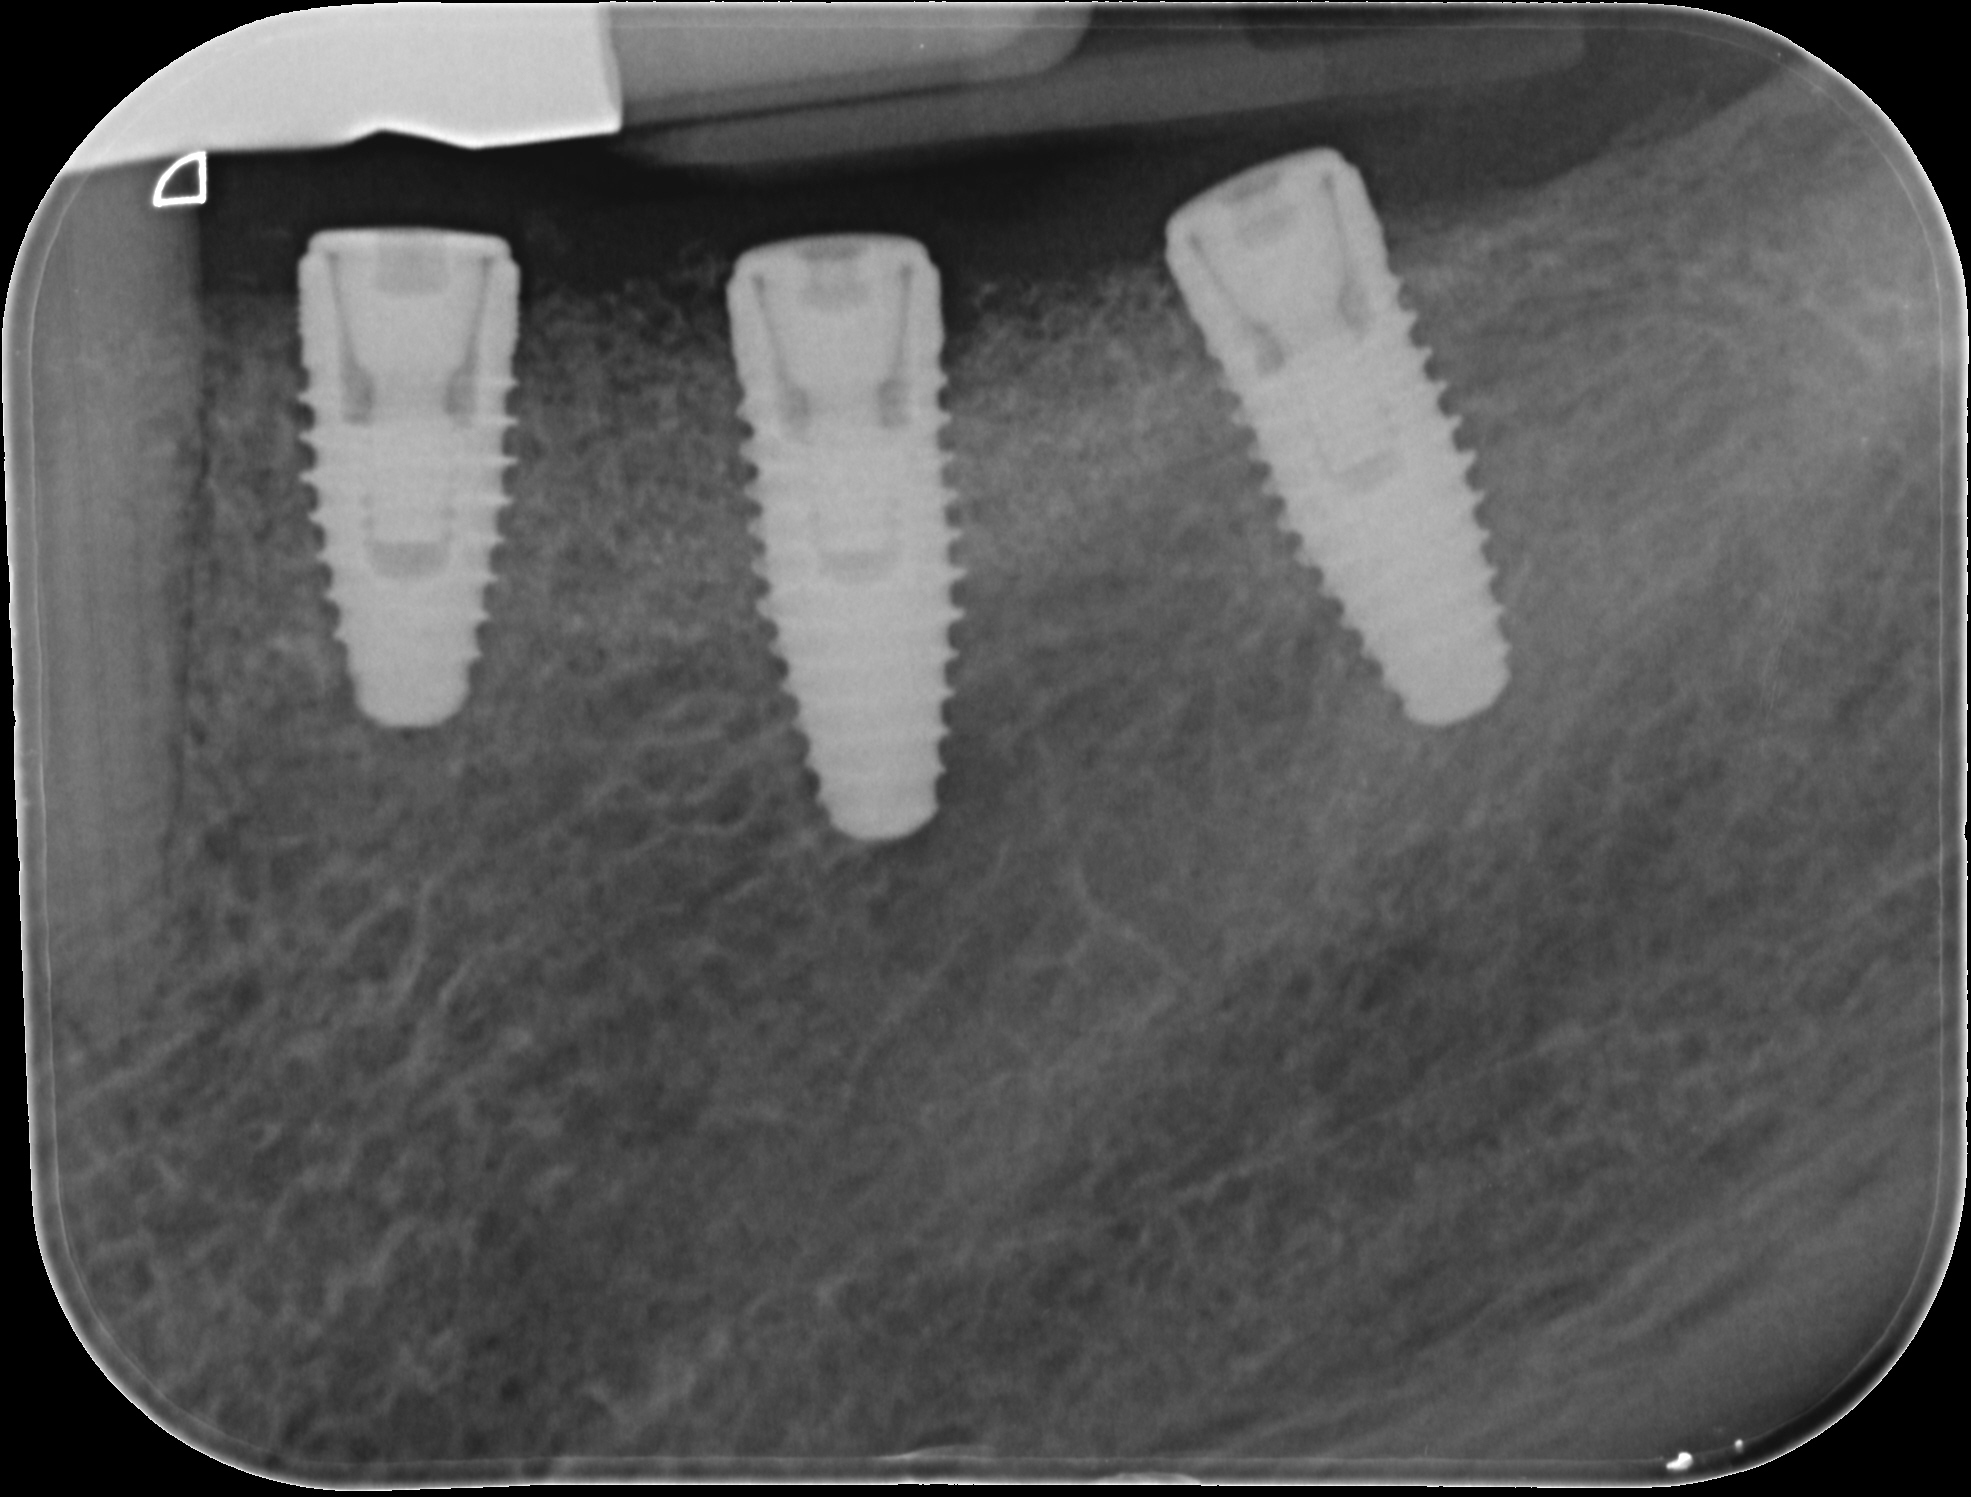

Replacement of a fixed partial denture with three implants

A 52-year-old patient is a referral and has been wearing an immediate provisional partial denture after replacement of her worn and fractured fixed partial denture. As a definitive treatment solution, the patient desired "beautiful and long-lasting" implant-supported single crowns. Clinically the CT-scan revealed a very narrow bone crest ("knife-edge") in the 3rd quadrant. Implant placement has been planned with a simultaneous GBR procedure.